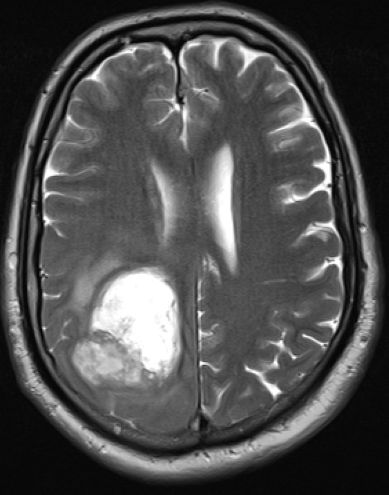

| Diagnostik | ![]() |

| Klinik | Glioblastome fallen durch Funktionsausfälle oder zerebrale Krämpfe auf. | Ausbreitung bevorzugt über große Faserbündel. 7-8% multifokal. Bei Erwachsenen frontal und temporal, bei Kindern Kleinhirn, Hirnstamm. | ||